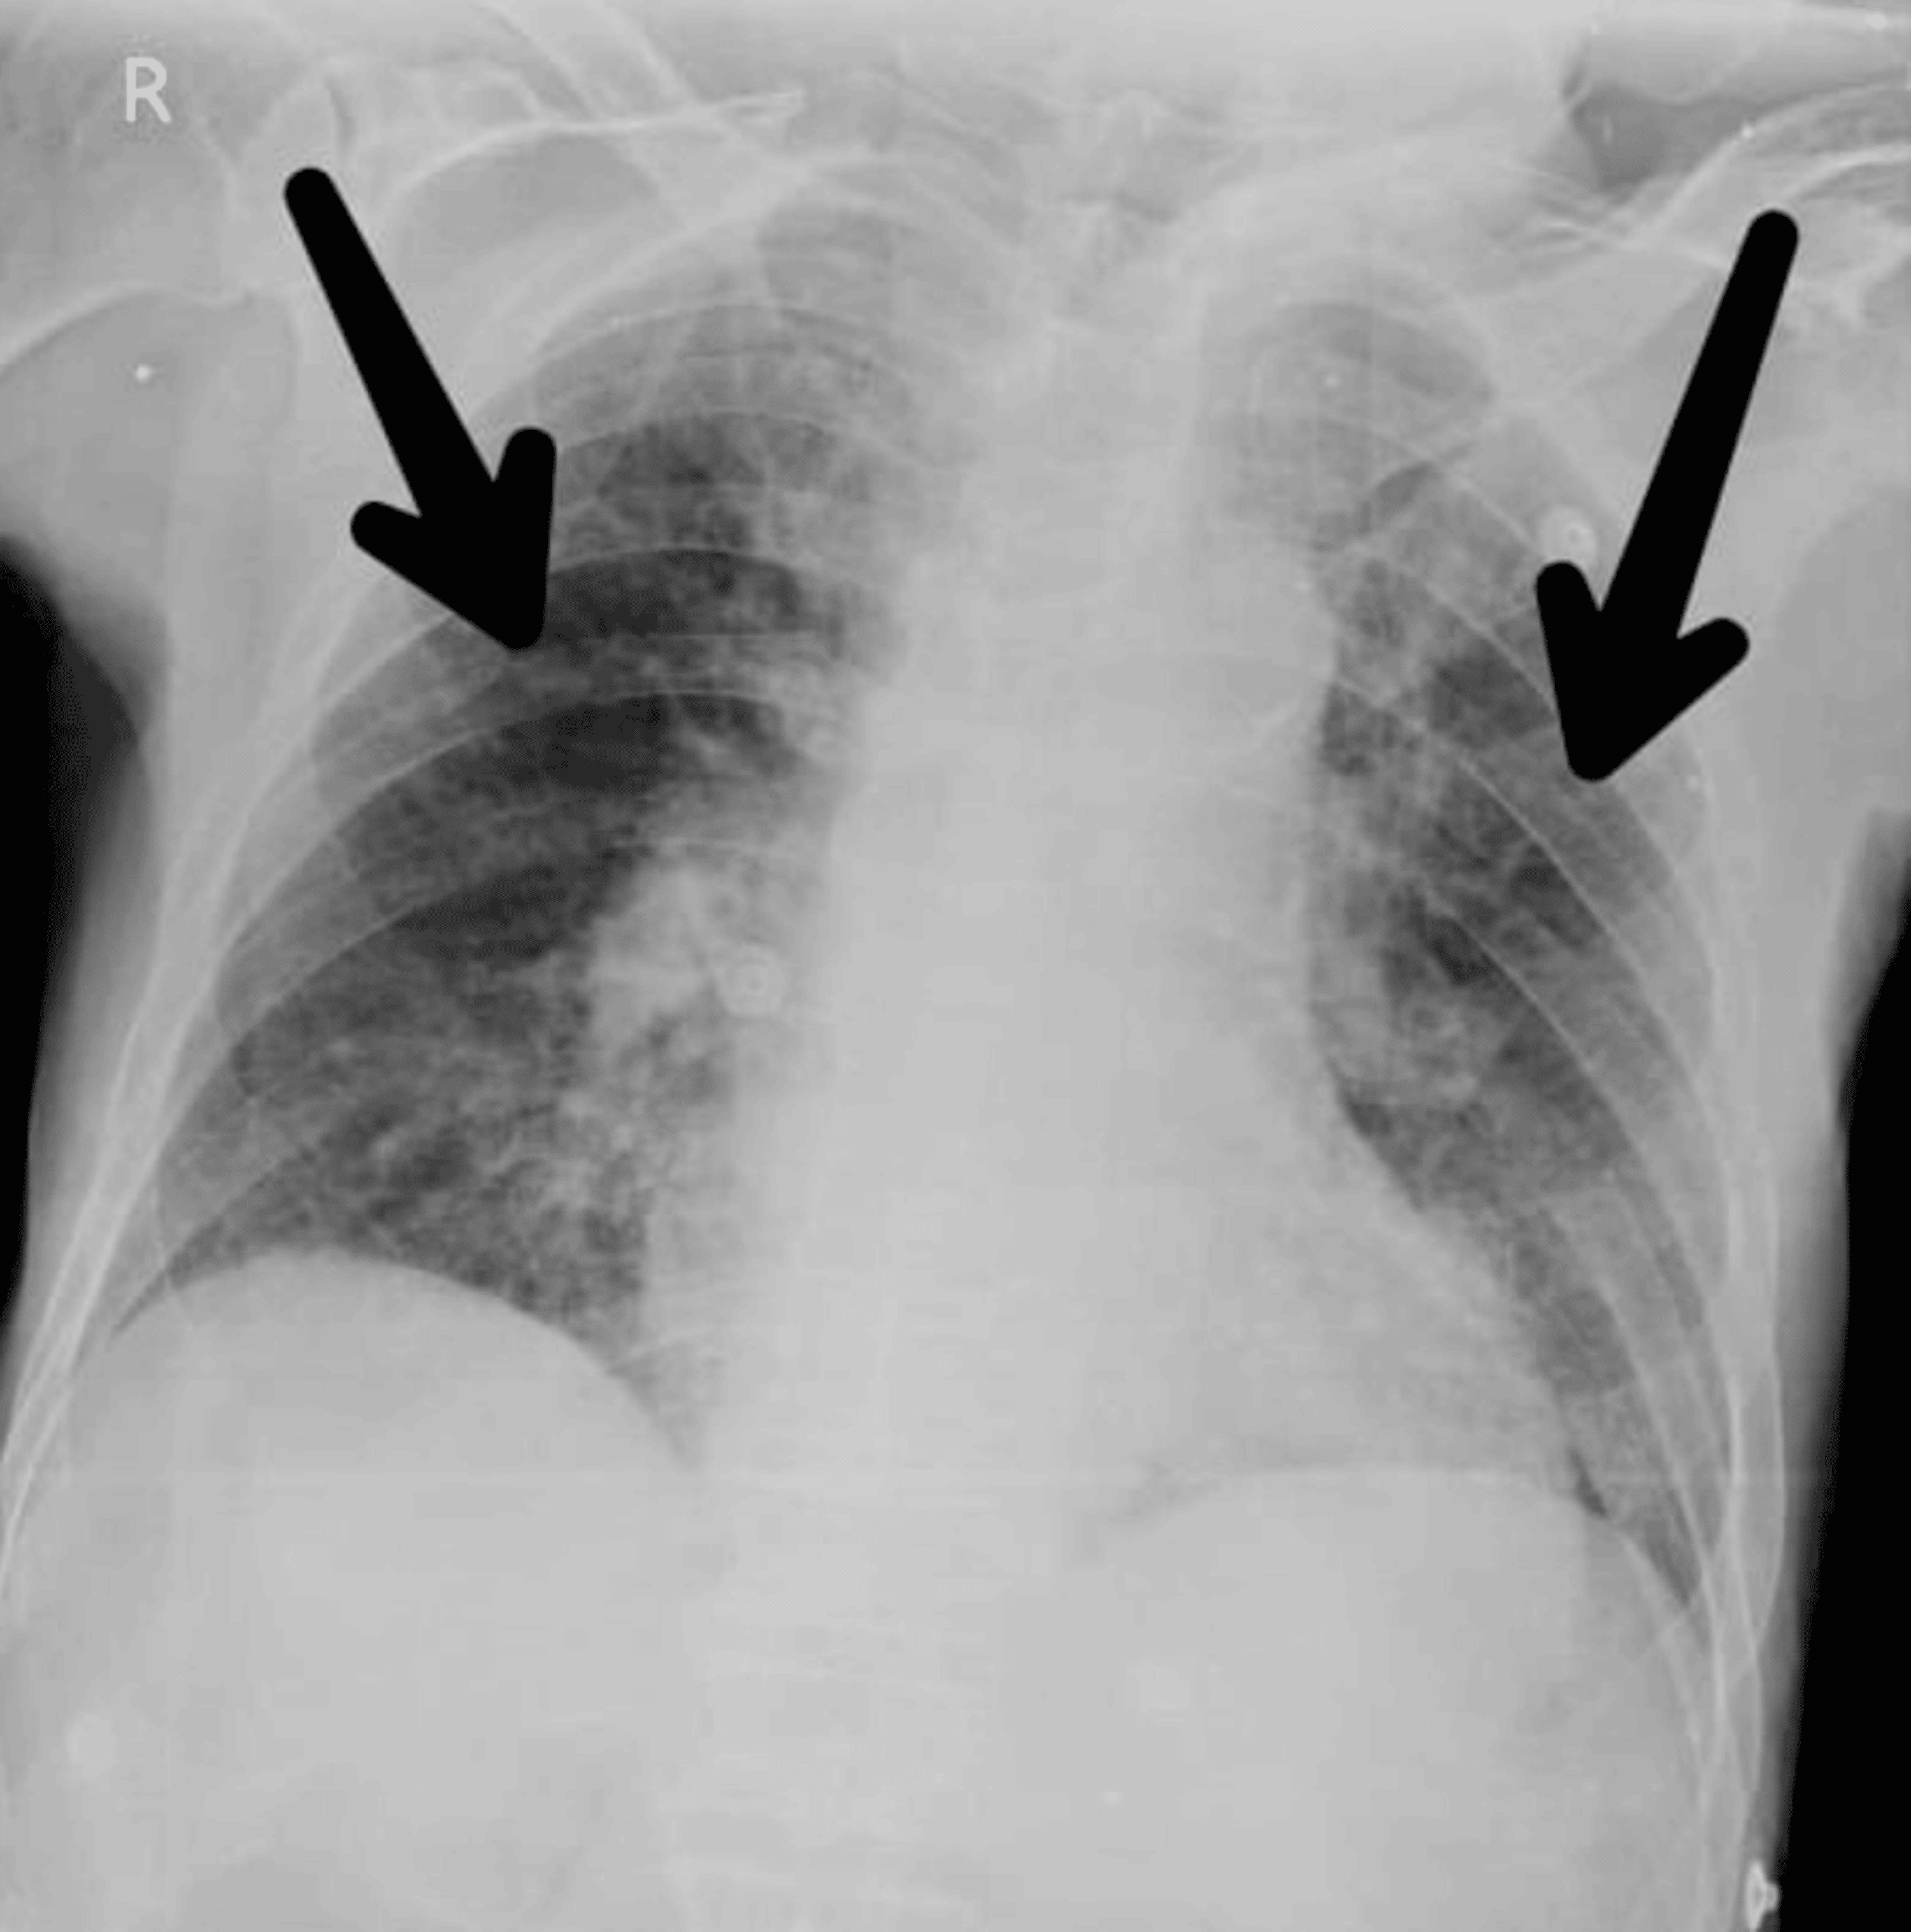

From www.researchgate.net

A Chest XRay of case 4 shows nodular opacity in both lungs. B Chest Does Chronic Bronchitis Show Up On A Chest X Ray (if you have shortness of breath, chronic bronchitis may limit the amount of oxygen circulating throughout your body.) you may. Imaging can show your provider if there’s any. Blood tests may be used to check for signs of. In some cases, recurrent bronchitis can lead to chronic respiratory issues. Spirometry is a common lung function test your provider may use. Does Chronic Bronchitis Show Up On A Chest X Ray.